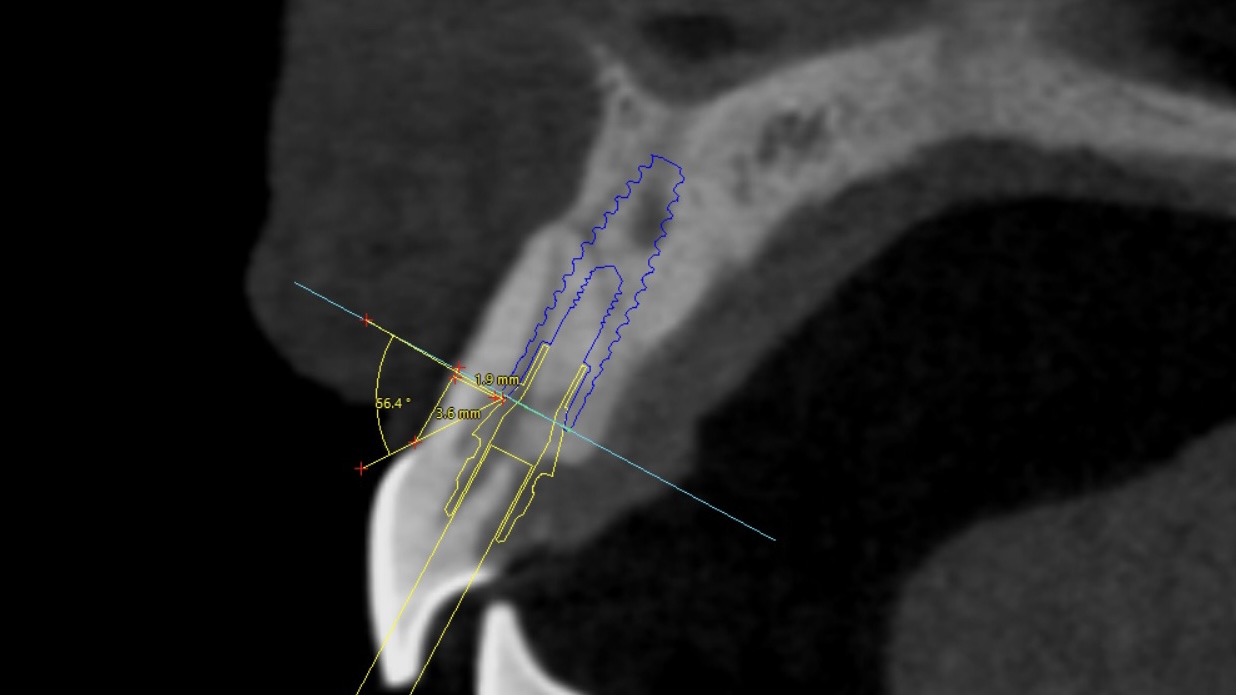

Planificación digital y Cirugía Guiada

En el Instituto Carranza, abrazamos la excelencia en la cirugía de implantes dentales a través de la planificación guiada, una herramienta esencial en nuestro enfoque innovador. Con tecnología de vanguardia, como imágenes tridimensionales y software especializado, personalizamos cada paso del procedimiento. Esta planificación minuciosa no solo mejora la precisión en la colocación de implantes, sino que también reduce riesgos y garantiza resultados estéticos y funcionales superiores. En el Instituto Carranza, nos enorgullece ofrecer una experiencia quirúrgica menos invasiva, acortando los tiempos de recuperación y brindando a nuestros pacientes una atención dental avanzada, segura y centrada en su bienestar integral.